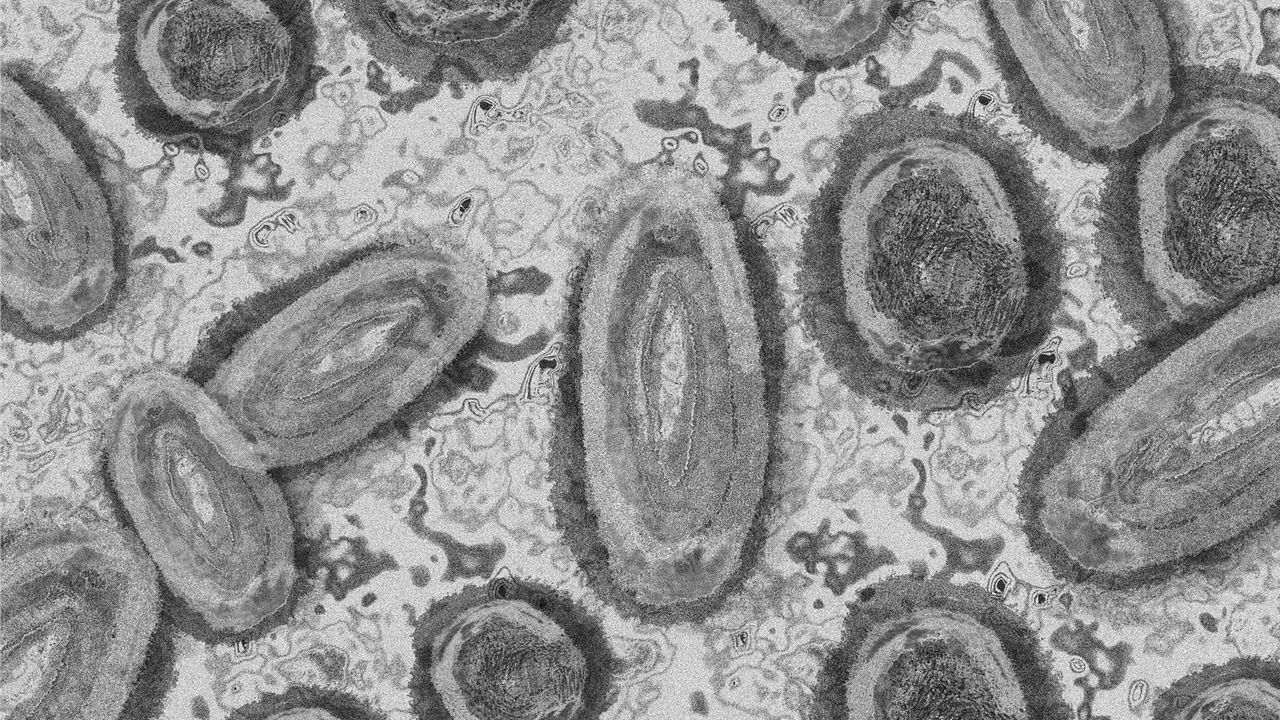

Ο συνολικός αριθμός των εργαστηριακά επιβεβαιωμένων κρουσμάτων ευλογιάς των πιθήκων...

Πάνω από 18.000 κρούσματα ευλογιάς των πιθήκων έχουν αναφερθεί παγκοσμίως από 78...